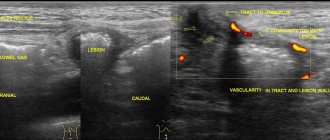

Диагностика

Если при гинекологическом осмотре пациентка рассказывает о характерных жалобах, врач может предположить наличие образования в уретре и направит на прием к урологу. В ходе диагностики первым делом врач осматривает уретру. Для заключения диагноза необходимо будет пройти исследования:

• собрать мочу для общего анализа, сделать ее посев;

• пройти ультразвуковое исследование (УЗИ) матки, придатков, всех органов системы мочевыделения;

• цитологическое исследование урины;

• в некоторых случаях прохождение МРТ;

• сдача мазка из мочеиспускательного канала;

• урофлоуметрия (измерение скорости мочеиспускания);

• эндоскопическое исследование уретры и мочевого пузыря (уретроцистоскопия).

Опираясь на полученные результаты в ходе диагностики, врач подтвердит либо ниспровергнет диагноз.

• УЗИ с использованием трансвагильнального датчика;

• уретроскопию.